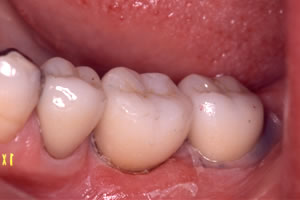

![]() 印象時